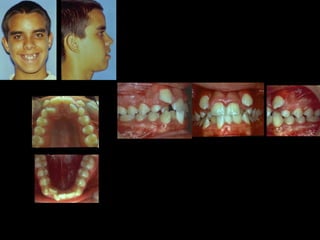

Valoración Clínica de la Paciente

En términos generales podemos decir que la

paciente tiene una cara armónica y aceptable,

sin embargo observaciones métricas delatan:

Laterognatia, manifestada por 3 grados de desviación del

Mentón con respecto a la línea media real.

Hipoplasia moderada del maxilar del lado derechoHipoplasia moderada del maxilar del lado derecho

Perfil cóncavoPerfil cóncavo

Ligera incompatibilidad labialLigera incompatibilidad labial

Depresión malarDepresión malar

La paciente muestra una franca disgnatia, clínicamente

observamos malposición dentaria secundaria a la falta de

armonía máxilomandibular.

Marcada Clase III

Hábito Lingual

Sobremordida horizontal: –1.5 mm

Sobremordida vertical: + 1 mm.